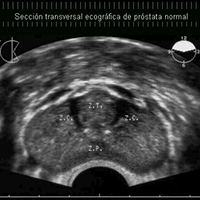

Es el procedimiento destinado a descartar la presencia de un cáncer prostático en aquel varón en el que se presenten criterios de sospecha clínica del mismo, bien sea por alteración del tacto rectal, elevación de los niveles de PSA o hallazgos sospechosos por RMN.

Se realiza por vía transrectal y control ecográfico, bajo anestesia local o sedación. Se obtienen de 8 a 12 cilindros por cada lóbulo prostático y la prueba se realiza en régimen ambulatorio.